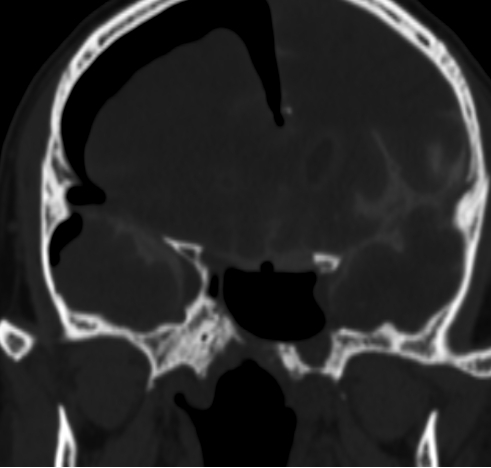

我院PET-CT检查显示鼻咽周围骨质改变,未见异常代谢增高,无肿瘤复发;左侧颞叶、左侧岛叶及左侧鞍旁片状低密度影,伴代谢稀疏,提示放射性坏死。脑室造影检查显示颅内积气,前颅底鞍结节颅骨缺损,脑脊液漏可能(图1-3)。MRI检查显示左侧颞叶内侧面不规则强化病灶,考虑放射性脑坏死改变(图4)。